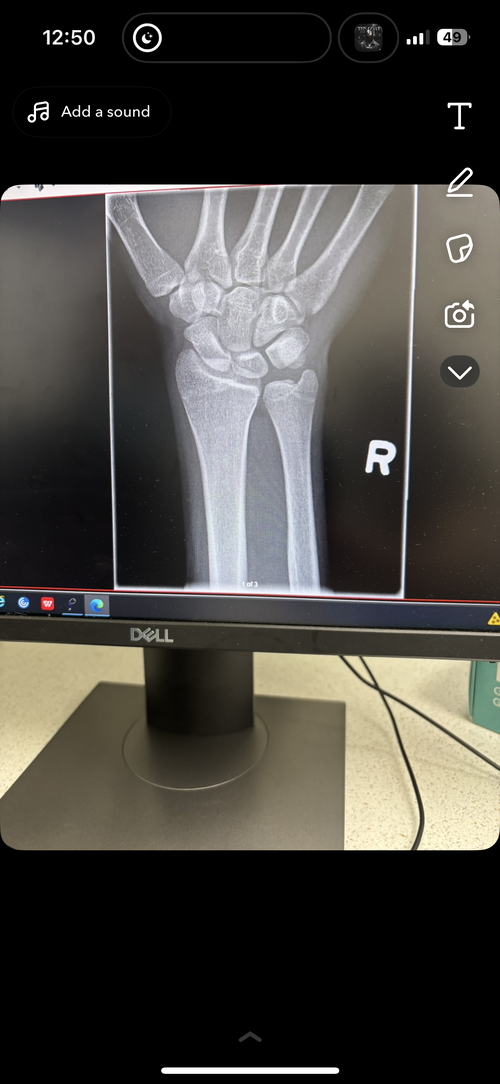

Bone plates gh and height

are my wrist bone plates closed ? I’m 18 and do you think any of my other plates would be open, would taking gh infinigrib and an ai benefit me at this point. Or would it cause harm to me from side affects I hear if you take gh after closure it may just harm you more then it helps u and for me I’m not for sure if all my plates are closed should I hop on?

Yours appear to be closed to me.

they’re closed but u should get ur knees checked, they are your last hope, if they’re open u might have a small window of growth left